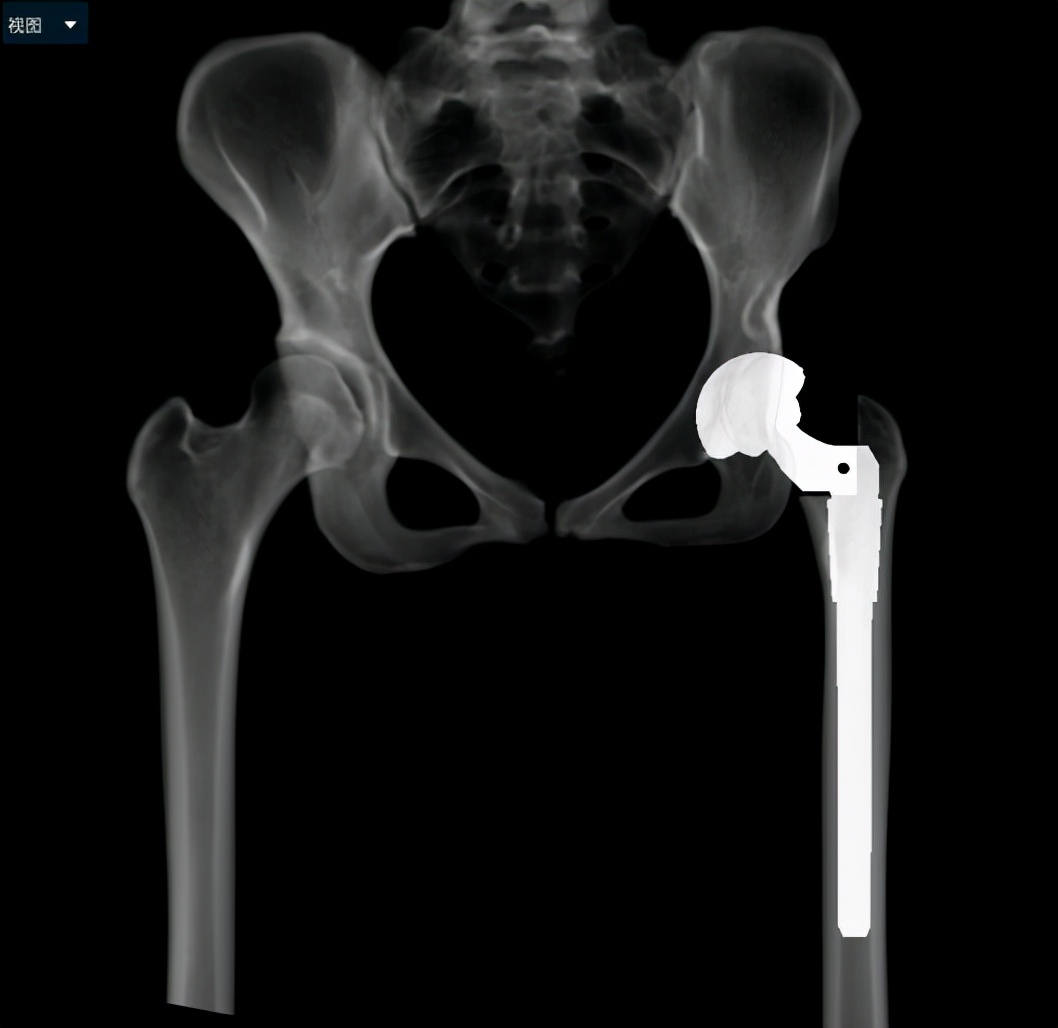

通过术前充分的准备,小张的手术也如约而至。当天在术中,毕教授和耿教授发现小张的患侧股骨头和髋臼都存在发育异常,没有软骨而且形状较不规则,难以契合,保髋方案不可取,于是只能采取方案二:全髋关节置换术。因为术前提前进行了规划,相应型号的假体也已经提前准备,髋臼假体及股骨假体安装得较为顺利。然而和预料的一样,在髋关节假体尝试复位时软组织张力较大,很难进行复位。因为在术前患侧股骨通过极限力量牵引验证了不截骨复位的可能性是存在的,为了能够让患者一期恢复腿长,避免二次手术,毕郑刚教授和耿硕副教授决定通过进行软组织的松解来复位,选择了不进行股骨截骨,但是考验手术技术。经过对髋关节周围软组织的松解后,最终假体复位成功,随后通过比对双下肢长度,提示等长,关节活动度良好,宣告着手术一期顺利完成。术后小张返回病房后,因为未进行截骨仍有软组织张力大致神经血管等损伤的风险,术后嘱其行患肢适度屈髋屈膝位来减缓软组织张力,2~3周内逐渐伸直。术后通过查体,小张并未出现神经的损伤症状,手术圆满成功。

(术后X线)